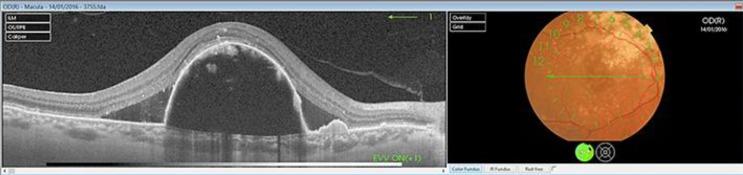

息肉样脉络膜血管病变(PCV)是新生血管性年龄相关性黄斑变性的一种亚型,其特征是具有动脉瘤样息肉样脉络膜血管病变的异常分支血管网络。PCV在亚洲人群中比在白种人中更普遍,这可能解释了其在西方国家诊断不足的原因。关于不同抗血管内皮生长因子(抗VEGF)药物对PCV疗效的证据很少,这些研究大多在亚洲初治患者中进行。雷珠单抗是第一种证明光动力疗法(PDT)联合抗VEGF在诱导亚洲PCV患者息肉消退方面优于PDT或抗VEGF单药治疗的抗VEGF药物。其他抗VEGF药物的疗效研究较少。已有对雷珠单抗耐药的报道。阿柏西普提供了另一种靶向脉络膜新生血管病变的机制。一名75岁的白种女性到我们诊所就诊,通过吲哚菁绿血管造影被诊断为PCV。采用玻璃体内注射0.5mg雷珠单抗负荷剂量,随后在第4个月以标准能量密度进行PDT,并在第5个月注射第四剂雷珠单抗的联合治疗未产生视觉或解剖学效果。在第6个月将治疗改为玻璃体内注射阿柏西普(每月3次负荷剂量2.0mg),随后在第9个月进行半能量密度PDT。光学相干断层扫描显示解剖学病变缓解。右眼视力提高到0.6。此后每两个月注射一次阿柏西普。1年的随访显示功能和解剖学稳定。

https://cdn.ncbi.nlm.nih.gov/pmc/blobs/cdb8/5903101/207fd4a6dbcf/cop-0009-0172-g03.jpg

https://cdn.ncbi.nlm.nih.gov/pmc/blobs/cdb8/5903101/766ed39b721e/cop-0009-0172-g01.jpg

https://cdn.ncbi.nlm.nih.gov/pmc/blobs/cdb8/5903101/88c8c7ce2763/cop-0009-0172-g02.jpg